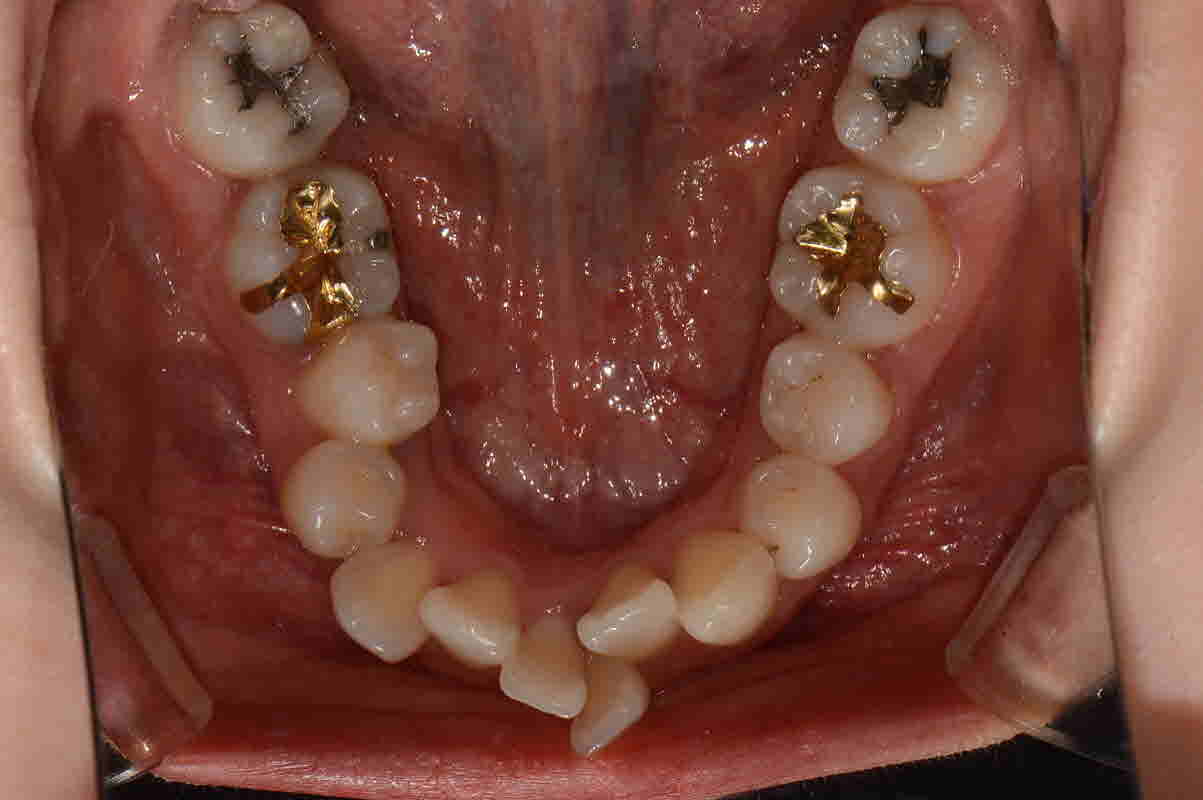

치아가 옹기종기 모여있어 삐뚤삐뚤한 치아를 바르게 교정하고자 내원해주신 김**님입니다. 발치교정으로 진행중이라 현재는 남아있는 발치공간을 닫는 중에 있습니다. 다른사람들에 비해 본인 치아는 많이 삐뚤어서 교정이 가능하신지 여쭤보시던게 엊그제 같은데 예뻐지는 치아배열을 보니 기분이 좋습니다.

교정시작 교합면

19년 3월 교합면